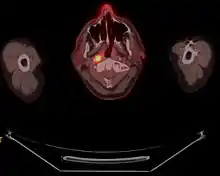

Staging of nasopharyngeal carcinoma is based on clinical and radiologic examination. Most patients present with Stage III or IV disease.

Stage I is a small tumor confined to nasopharynx.

Stage II is a tumor extending in the local area, or that with any evidence of limited neck (nodal) disease.

Stage III is a large tumor with or without neck disease, or a tumor with bilateral neck disease.

Stage IV is a large tumor involving intracranial or infratemporal regions, an extensive neck disease, and/or any distant metastasis. [16]